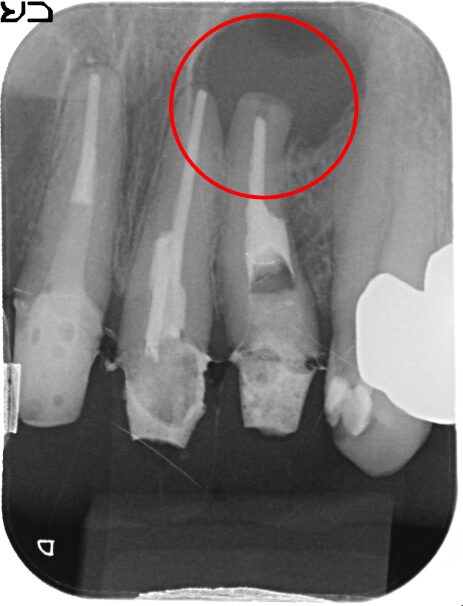

初診時

-

治療後

1年後

主訴

前歯の歯ぐきが腫れた。

治療の概要

根管治療では治らない歯に対して、根の先端を切除しそこから特殊な器具で穴をあけ、MTAという材料を充填し封鎖をはかりました。

1年後のレントゲンでは、根尖の病変がなくなり、骨ができています。